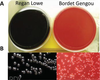

What is the Agar Medium which test for Bordetella pertusis (whooping cough)?

Bordet-Gengou (BG) Agar

-Red

Regan-Lowe Agar

-Black